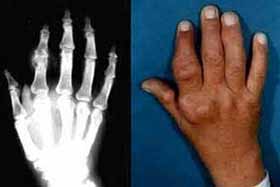

检查报告:血沉ESR:22mm/h,抗链球菌溶血素"0"ASO 阴性(-),类风湿因子 RF 阳性(+)。X线片示,患者右手手指关节肿胀,关节间隙狭窄,骨质受损。

(图:李先生治疗前,右手手指关节肿胀,有明显触痛感)

查体记录:双手手指关节肿胀、疼痛,关节周围皮肤颜色发红,皮温高,肘关节弯曲疼痛,脚趾关节疼痛,行走困难。按压关节有明显疼痛感。